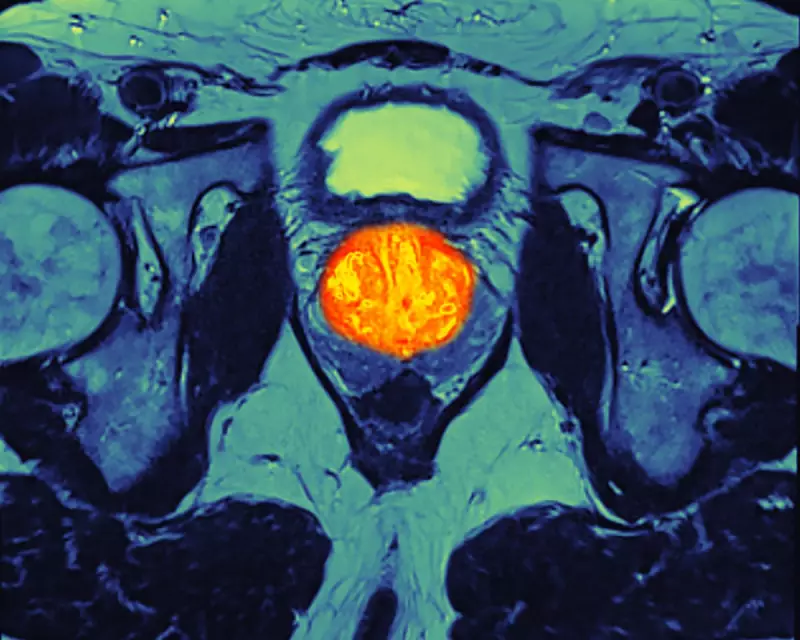

Prostate cancer is the most common cancer in men in the UK, with around 55,300 new diagnoses and 12,200 deaths annually. The expansion of abiraterone, which works by starving cancer cells of the hormones they need to grow, marks a significant shift in clinical approach.

The decision follows compelling clinical evidence. A major trial led by University College London and the Institute of Cancer Research found that when given alongside standard therapy, abiraterone could halve the risk of the cancer returning and cut the risk of death by 40% for men with non-metastatic disease.